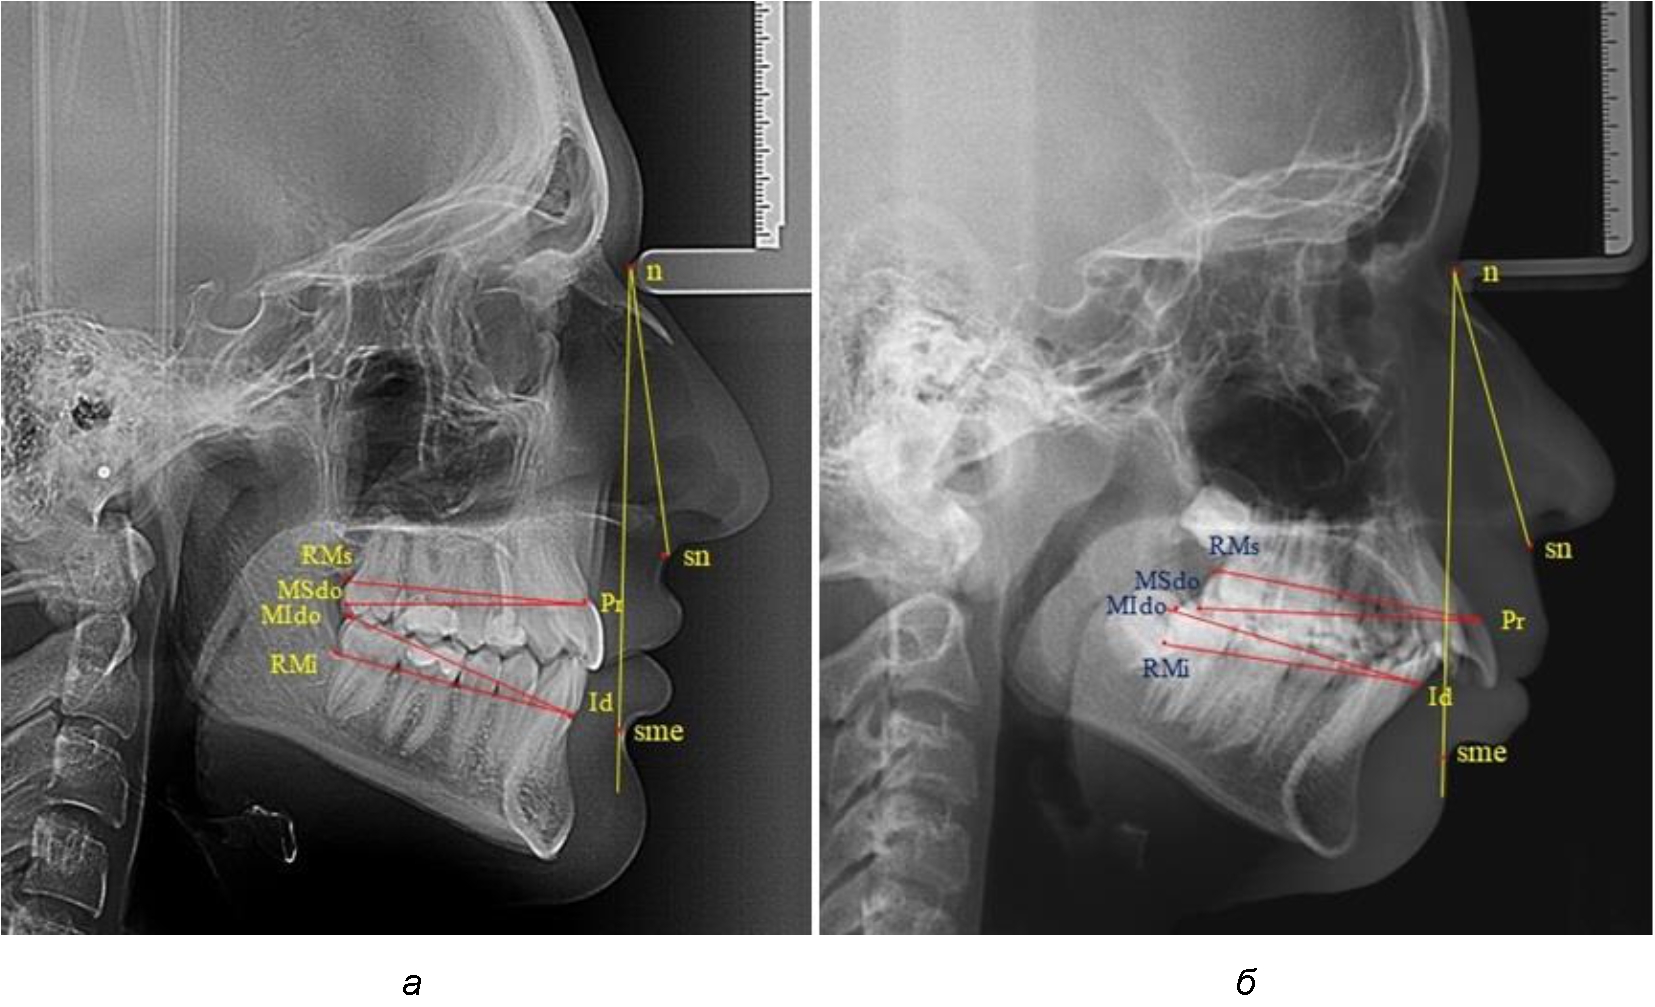

При определении альвеолярных и альвеолярно-дентальных размеров челюстей в переднезаднем направлении на верхней челюсти определяли положение пришеечной точки резца, которое обозначалось как точка простион (Pr). На нижнем резце альвеолярная точка обозначалась как инфрадентале (Id).

В заднем отделе зубных дуг ориентировались на положение вторых моляров. На верхнем моляре дистальную точку окклюзионного контура обозначали как «MSdo». Дистальную окклюзионную точку второго моляра нижней челюсти (дистально-окклюзионный молярный ориентир) обозначали как «MIdo».

Измеряли межальвеолярное расстояние на верхней челюсти (Pr-RMs) и на нижней челюсти (Id-RMs) и сравнивали показатели между собой. Альвеолярно-окклюзионный размер на верхней челюсти (Pr-MSdo) сравнивали с аналогичным параметром нижней челюсти (Id-MIdo). При анализе 32 телерентгенограмм с дистальной окклюзией использовали те же ориентиры (рис. 1).

Рис. 1. Точки и линии телерентгенграмм при физиологической (а) и дистальной (б) окклюзии

При физиологических вариантах прикуса дистальные окклюзионные точки моляров, как правило, располагались практически рядом, в то время как при дистальном соотношении нижние моляры анализируемый окклюзионные точки, как правило, располагались позади верхних.